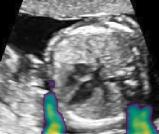

Fig. 6 compares the shadow confidence maps of the state-of-the-art methods and the proposed methods. RW and have the same parameters as used for Table I. The shadow confidence maps of the baseline, the proposed method and the proposedAG method are generated directly from input shadow images by confidence estimation networks. Overall, the proposed method and the proposedAG method achieve more visually reasonable shadow confidence estimation than the baseline and the state-of-the-art on different anatomical structures shown in Fig. 6. The proposed method and the proposedAG method are able to highlight multiple shadow regions while the RW algorithm shows limitations for most cases, especially for disjoint shadow regions.

Row I in Fig. 6 shows a fetal brain image from . The confidence estimation of shadow regions from the baseline, the proposed method and the proposedAG method are similarly accurate since we use fetal brain images to train the confidence estimation networks in these three methods. These outperform [16] and [22]. Rows (II-IV) in Fig. 6 show shadow confidence maps of non-brain anatomy from , including lips, abdominal and cardiac. The baseline failed on unseen data during inference. However, the proposed methods are able to generate accurate shadow confidence maps because of the generalized shadow features obtained by the shadow-seg module. Furthermore, the “Lips” example shows that our method is capable of detecting weaker shadow regions that have not been annotated in manual segmentation. This indicates that the confidence estimation network has learned general properties of shadow regions.